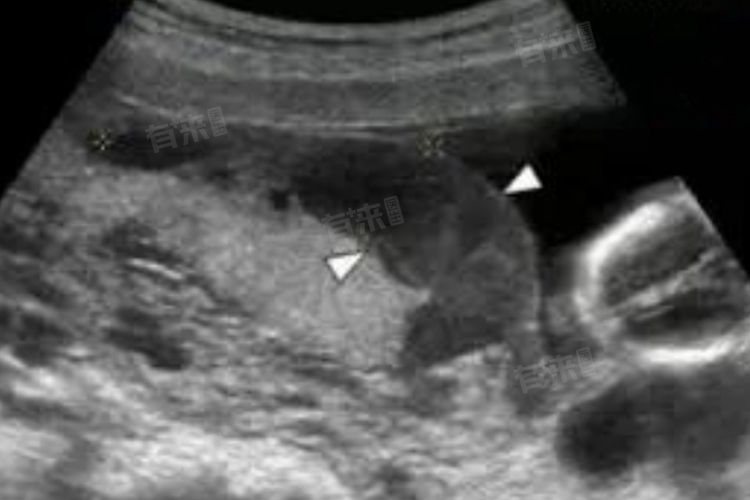

胎盘血池也称为胎盘血窦,是发生于胎盘的一种异常结构,表现为胎盘局部的静脉扩张,血液在其中淤滞而形成的静脉池,通常与胎盘发育异常、外力撞击等方面有关。